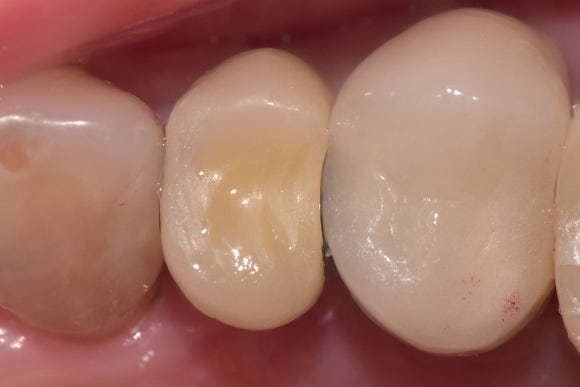

20250415

아주 좁은 공간이었지만,

정교하게 임플란트(=인공뿌리)를 식립한 결과

꼭 맞는 머리를 만들어 올릴 수 있었습니다.

브릿지를 만들었어야 했다면

더 많은 비용과 시간이 필요했을 것입니다.